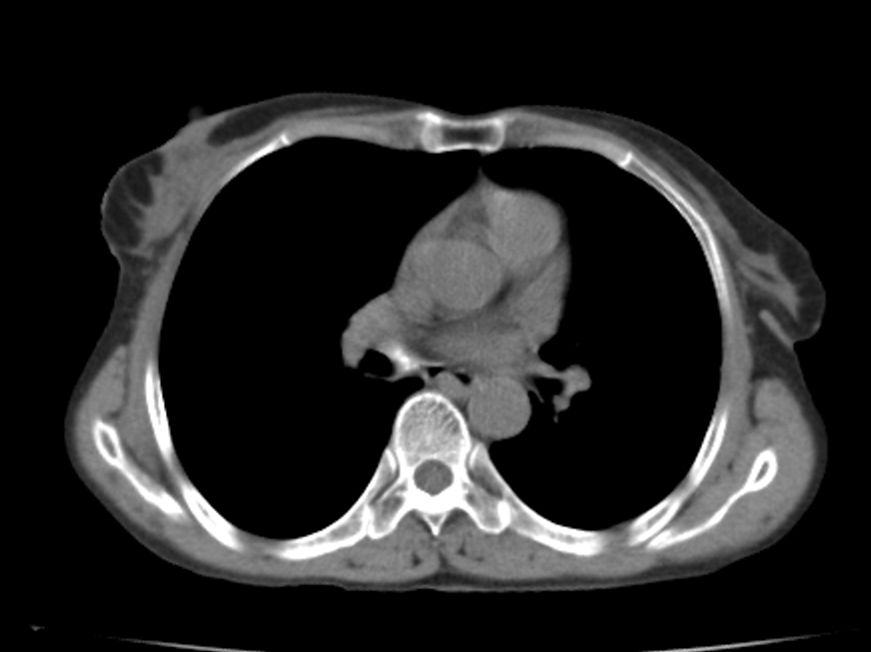

标题: CT21609:右乳包块1年,请各位讨论分析一下,乳腺CA, [打印本页]

标题: CT21609:右乳包块1年,请各位讨论分析一下,乳腺CA,

考虑---右乳癌并胸壁、肋骨、双肺转移。

考虑乳腺癌侵犯肋骨、胸壁及两肺转移可能性大。

右乳癌并胸壁、肋骨、双肺转移。

考虑右侧乳腺癌侵犯肋骨、胸壁及两肺转移。

支持考虑---右乳癌并胸壁、肋骨、双肺转移。

考虑右侧乳腺癌侵犯肋骨、胸壁及两肺转移可能。

考虑右侧乳癌并胸壁、肋骨及双肺多发性转移。